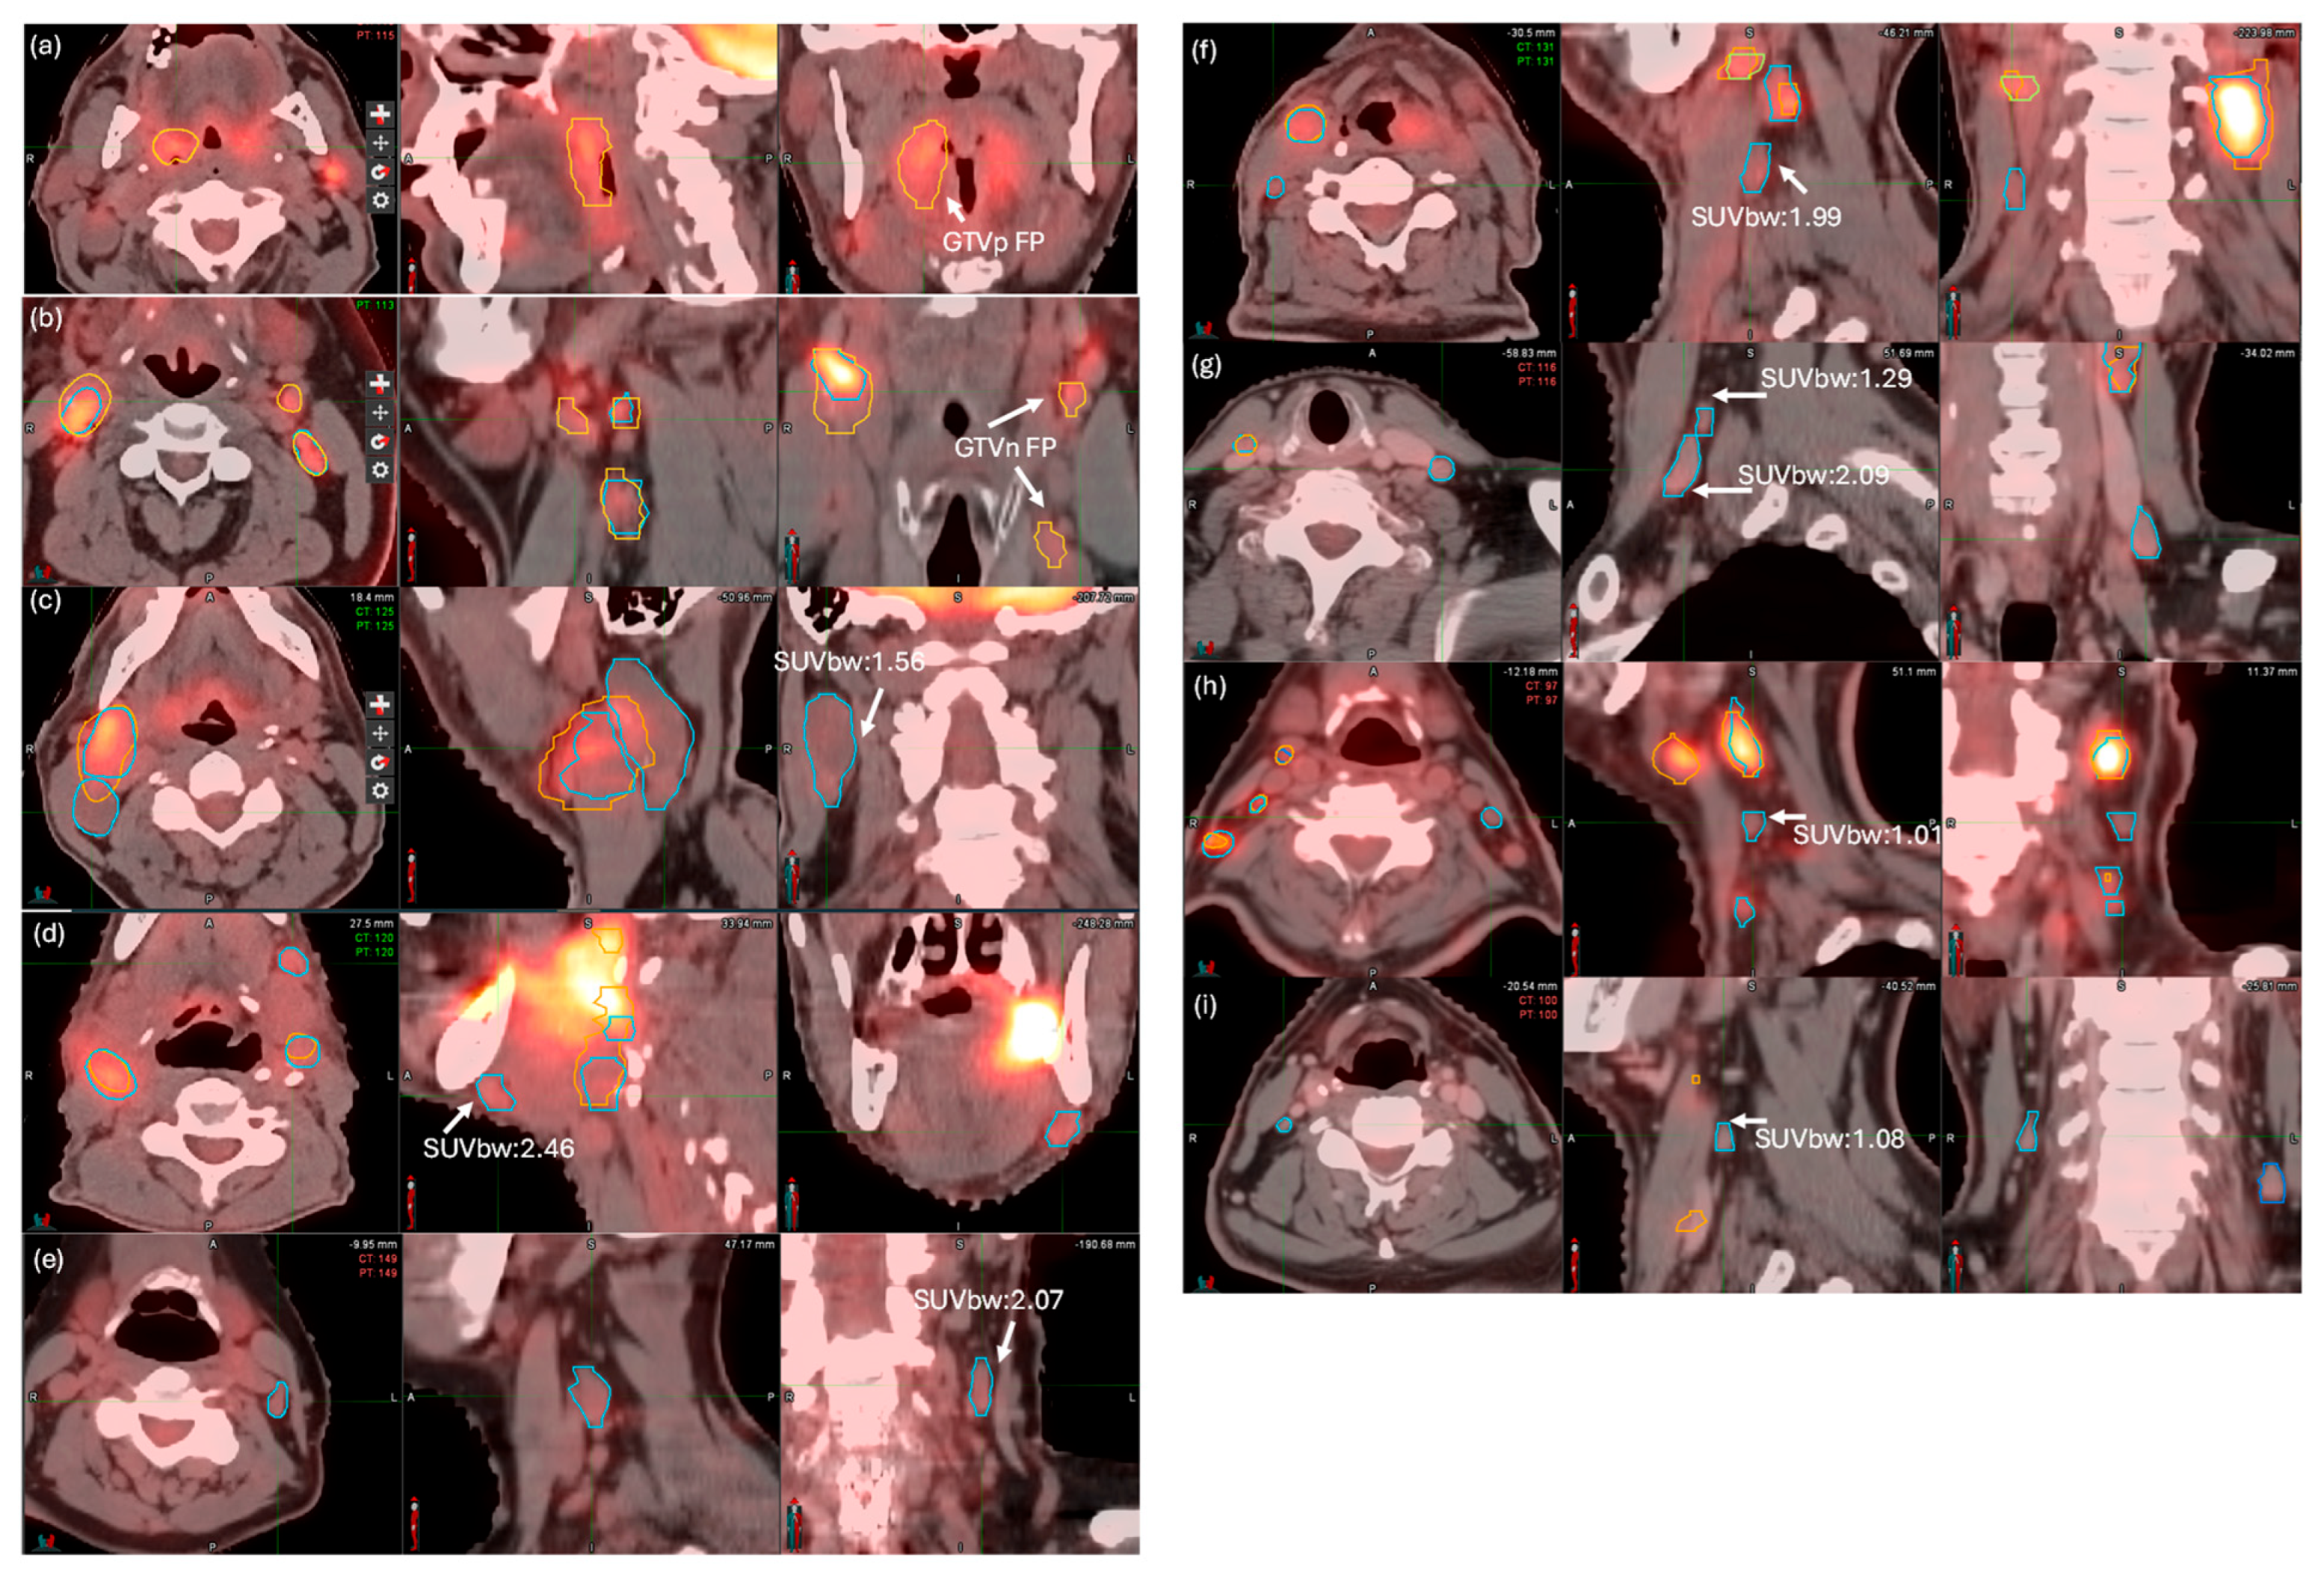

3.3. FP Ruling Out and FN Detection Results